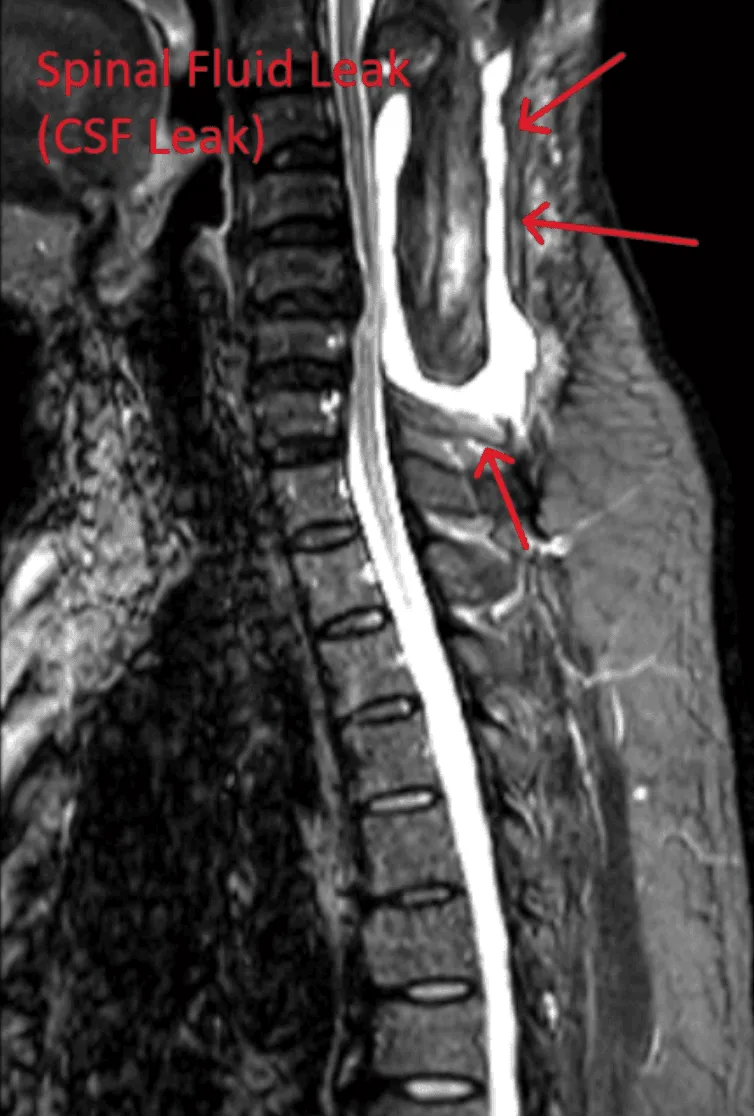

MRI showing a spinal fluid leak with red arrows indicating the affected area.

Spinal Fluid Leak

Accidental puncture of the dural membrane can cause cerebrospinal fluid leaks, leading to severe positional headaches and potential need for additional procedures.